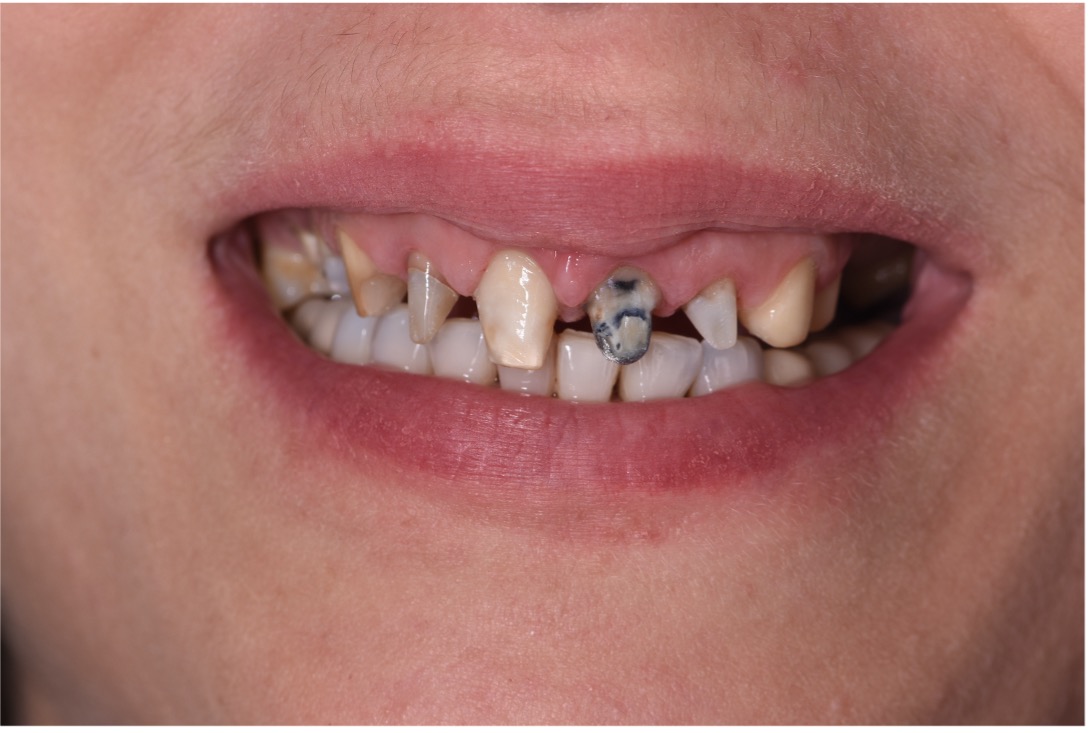

• Chief Complaint: Gummy Smile and Old Crowns

• Initial Diagnosis: Excessive Gummy Smile and Discolored old crowns

Step 1: Diagnostic Assessment and Smile Design The treatment began with a comprehensive evaluation of the patient’s smile using facially guided diagnostics. The Facial Flow Concept was employed to assess the relationship between the patient's facial structure, lips, smile arc, and gingival display. SmileFy software was utilized to generate a 2D digital smile simulation.

This visualization allowed both the clinical team and the patient to preview the planned esthetic outcome. It also provided a platform for mutual understanding and expectation management, forming a blueprint for all subsequent steps.